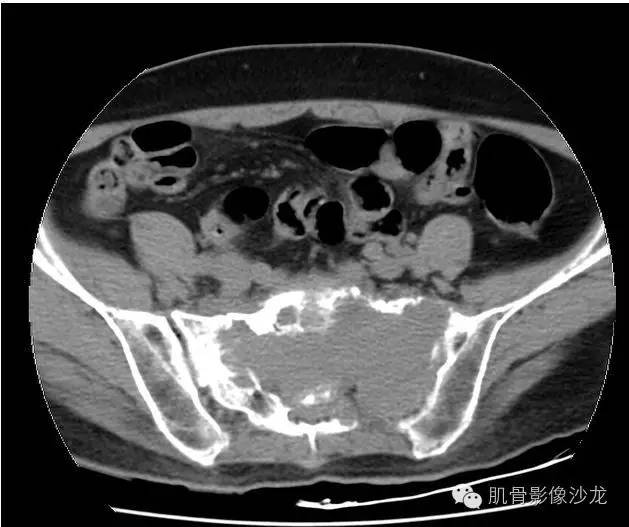

女,50岁,腰痛伴左下肢放射痛4个月

骶骨巨大骨质破坏区,破坏区软组织肿块密度较均匀,边缘不规则残留少许骨皮质,膨胀性改变不明显,肿块基本局限于骨破坏区内。

最后病理:高分化浆细胞瘤

这个溶骨性骨质破坏征象,骶骨的形态还是保留的 所以影像也像浆细胞瘤 但是 转移瘤必须鉴别 转移瘤万能的模仿者